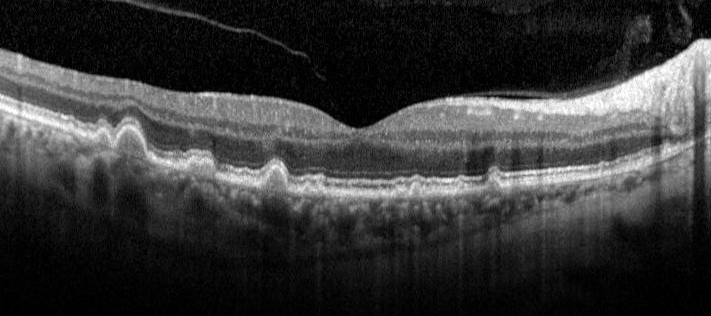

On OCT imaging, drusen appear as dome-shaped elevations of the RPE. Over time, drusen can increase in size and coalesce to become confluent. Pigmentary abnormalities can present as RPE disturbance, thickening or attenuation. In cases of hyper-pigmentary abnormalities, hyper-reflective foci in the outer nuclear layer and posterior shadowing can be found. Conversely, hypo-pigmentary changes may result in an increased transmission of the OCT signal.